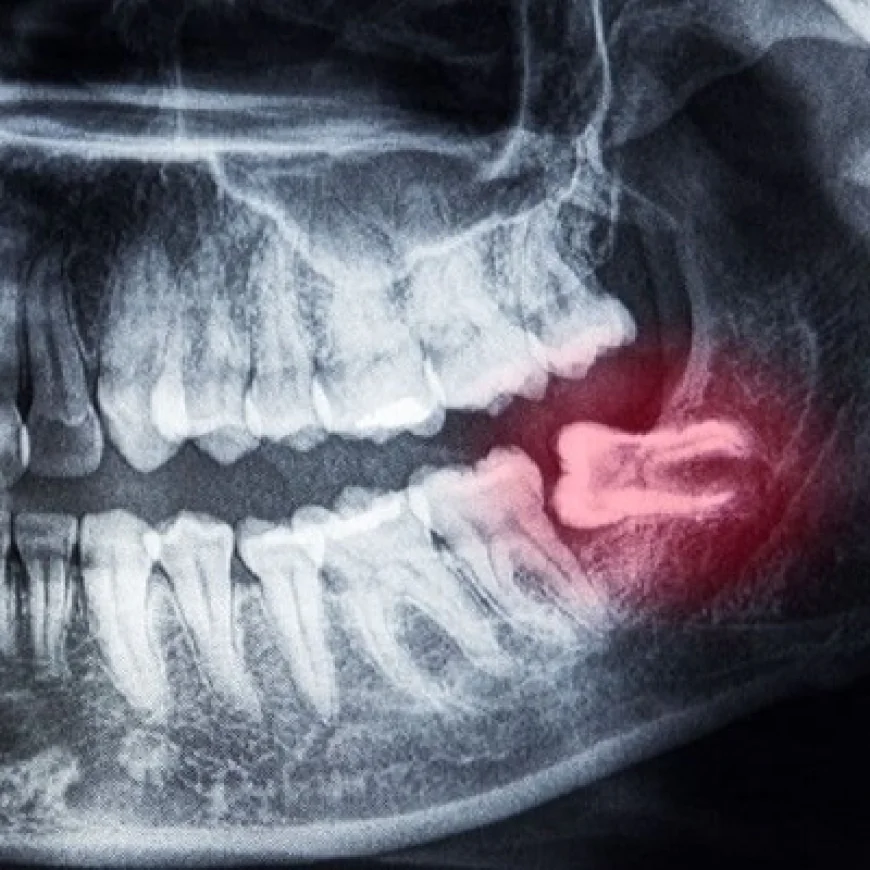

Dental Panoramic X-Ray in Dubai offers a full-mouth image that helps detect dental issues such as impacted teeth, jaw problems, and bone abnormalities. It is a quick, painless, and essential diagnostic tool used by dentists for accurate treatment planning and ensuring comprehensive oral health care.

A panoramic X-ray, also called an orthopantomogram (OPG), is a type of dental imaging that captures the entire mouth—including teeth, jaws, temporomandibular joints (TMJ), and surrounding bone structures—in a single, wide image. Unlike small, intraoral X-rays, a panoramic scan provides a comprehensive overview, making it ideal for treatment planning in complex procedures such as dental implants.

Sometimes, underlying problems like cysts, impacted teeth, or infections are discovered during imaging. Detecting and treating these issues before implant surgery ensures long-term success.